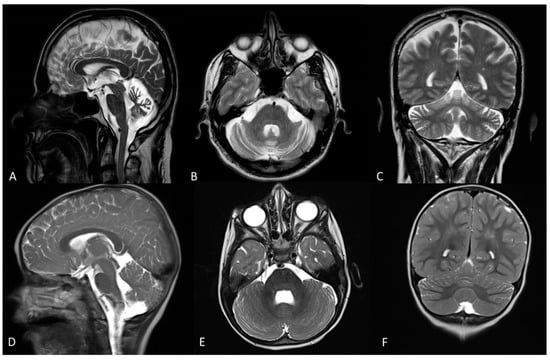

| Seizures Clinical course Brain MRI | No Slowly progressive CA | No Slowly progressive CA | No stable mild CA |